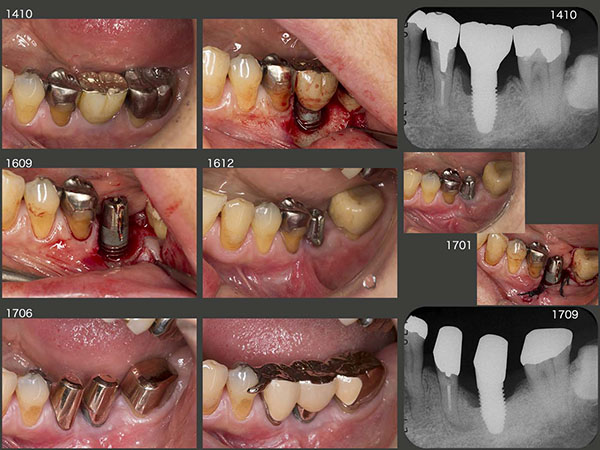

1994年11月初診,当時47歳の女性.2007年5月に左下6の近心根を歯根破折にて抜去した.そして,11月に直径5mm,長さ10mmのインプラントを植立した.スライド上段右端に08年1月,硬質レジン前装冠装着時を示す.今になって思うと,顎堤の近遠心的な距離があるので直径5mmを選択したが,頰舌側の距離がないことから,骨の水平的拡大が必要,あるいはこのサイズのインプラントの適応症ではなかったと反省している.そのためか,数年後にインプラント周囲炎が発症してしまった.

2014年10月までインプラントの経過をみていたが,この時点で歯周ポケットが最大8mmとなったため,フラップを開け,中の掻爬を行った.しかしその後も改善せず,16年9月に硬質レジン前装冠を外し,再度掻爬を行った.清掃しやすい環境にして3ヵ月経過をみたが,まだ改善傾向を示さなかった.そこで12月にまず頰小帯を切除し,その後に掻爬術を施す治療計画を立て,患者さんに協力頂けるようお願いしてみた.快諾を得,背水の陣で3回目の掻爬を17年1月に行った.歯周ポケットは唇側でまだ5mm残っているが,歯肉の状態は改善した.6月,インプラントをロスしても対応できるように可撤式の補綴装置を装着した.

この患者さんは右咬みなのか,2015年7月に5mmであった右上5の歯周ポケットが16年2月には9mmと,歯周病が急に悪化した.そこで仕方なく右上5の抜髄を行い,自然挺出を行った.8月まで3ヵ月間挺出したのち,同月歯周外科処置を行った.歯周ポケットは3mm以下に改善したが,歯の動揺が残ったため,右上4と連結固定した.

右下には,右下6,7それぞれの遠心根を支台歯としたブリッジを装着していたが,06年に右下7の遠心根が保存困難となり抜去した.その後,右下6の遠心根は孤立歯の状態のまま10年が経過した.右側の大臼歯部の咬合接触面積が少ないことが,右上5の悪化に繋がったと反省し,今回は右下大臼歯部もしっかり咬合させることにした.まず,右下6の遠心根をアップライトし,歯軸を改善したのち,コーヌス義歯を装着した.